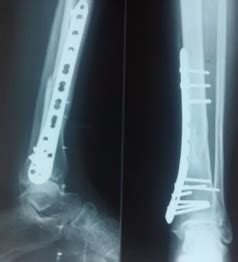

Figure 2: Pre and post operative x-rays of a patient with distal 3 rd ...